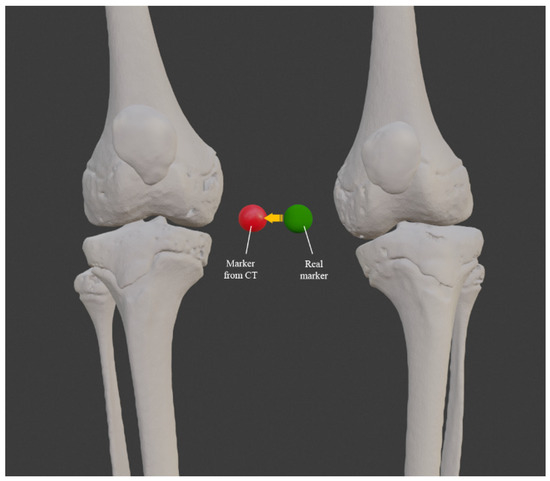

3.1. 3D Reconstruction of Patient-Specific CT Scan

3.3. Comparison between Standard and Custom Model

3.4. Virtual Surgical Simulation